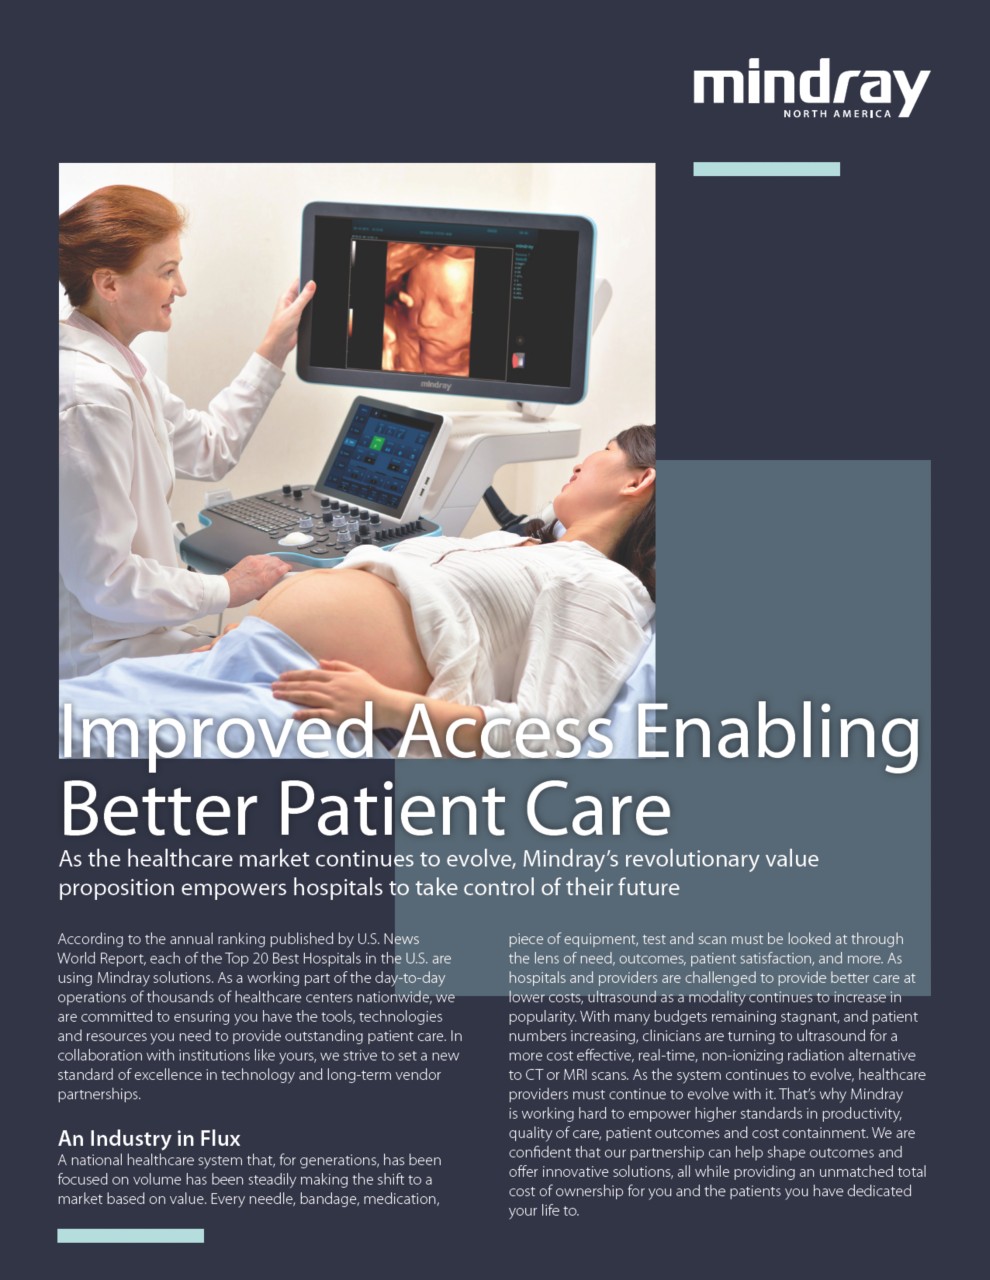

As the healthcare market continues to evolve, MindrayŌĆÖs revolutionary value proposition empowers hospitals to take control of their future.

According to the annual ranking published by?U.S. News World Report,?each of the Top 20 Best Hospitals in the U.S. are using?Mindray solutions. As a working part of the day-to-day operations of thousands of healthcare centers nationwide, we are committed to ensuring you have the tools, technologies and resources you need to provide outstanding patient care. In collaboration with institutions like yours, we strive to set a new standard of excellence in technology and long-term vendor partnerships.

A national healthcare system that, for generations, has been focused on volume has been steadily making the shift to a market based on value. Every needle, bandage, medication, piece of equipment, test and scan must be looked at through the lens of need, outcomes, patient satisfaction, and more. As hospitals and providers are challenged to provide better care at lower costs, ultrasound as a modality continues to increase in popularity. With many budgets remaining stagnant, and patient numbers increasing, clinicians are turning to?ultrasound?for a more cost effective, real-time, non-ionizing radiation alternative to CT or MRI scans. As the system continues to evolve, healthcare providers must continue to evolve with it. ThatŌĆÖs why Mindray is working hard to empower higher standards in productivity, quality of care, patient outcomes and cost containment. We are confident that our partnership can help shape outcomes and offer innovative solutions, all while providing an?unmatched total cost of ownership?for you and the patients you have dedicated your life to.